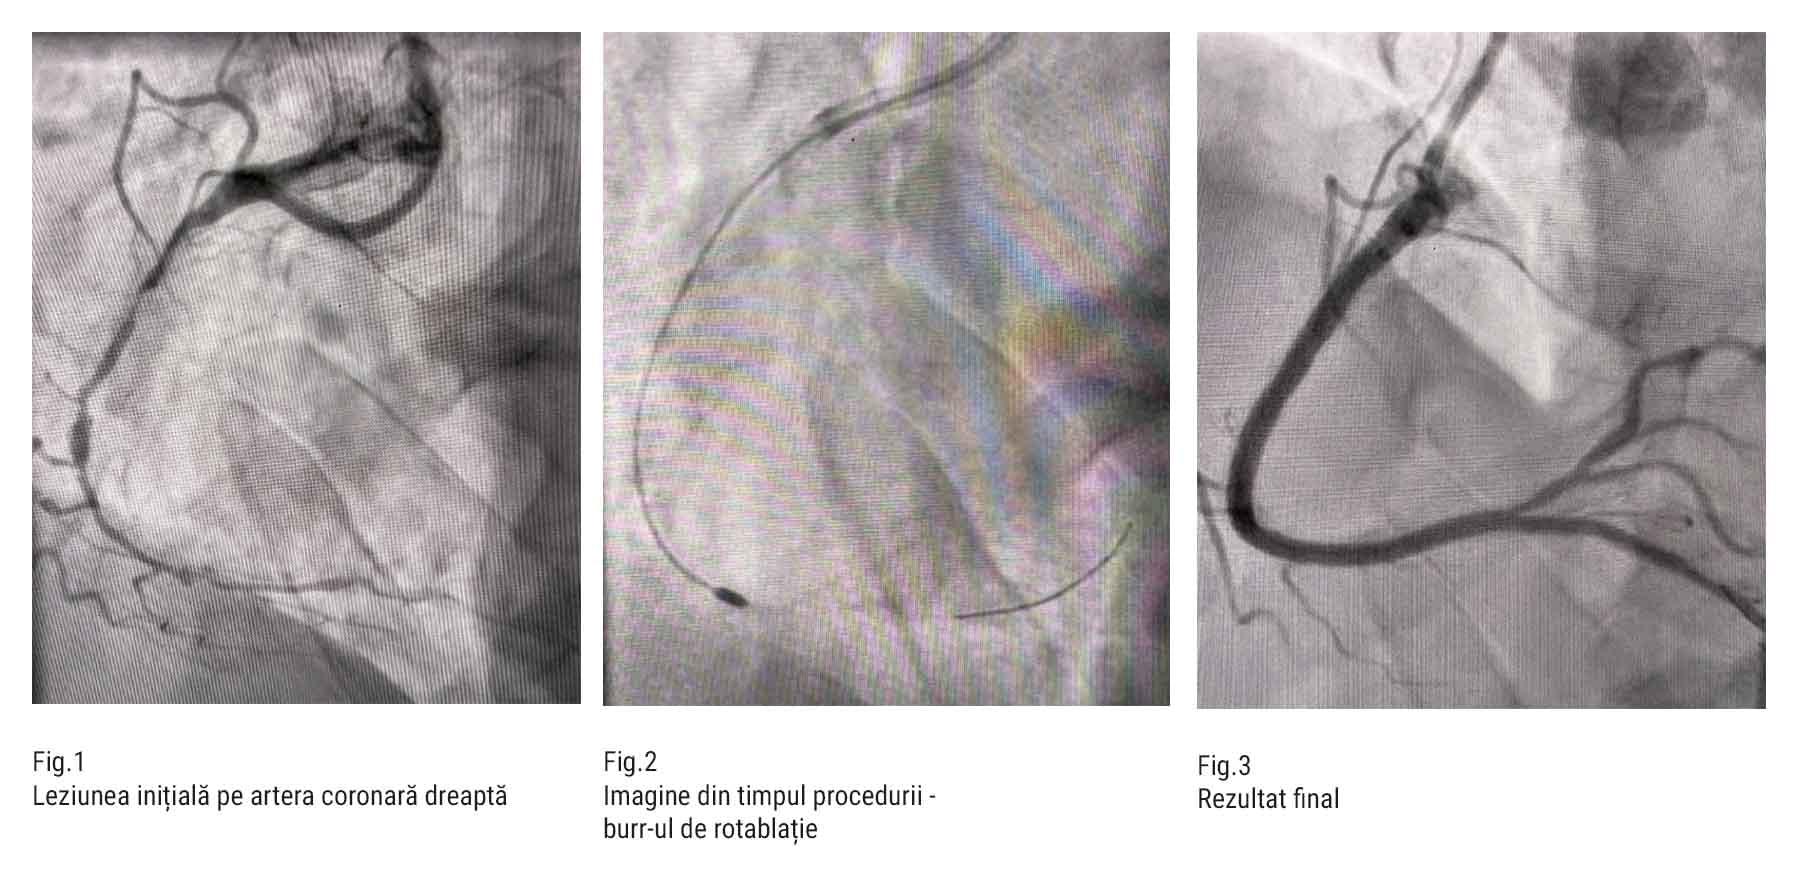

- ACD cu stenoze seriate de până la 90%

- Rotablație a arterei coronare drepte (ACD)

- Angioplastie cu implantare a 3 stenturi farmacologic active (DES) la nivelul ACD

Rotablația este o tehnică specializată de fragmentare a plăcilor de aterom calcificate, utilizată în leziuni foarte dure, unde dilatarea cu balon sau implantarea stentului standard sunt imposibile.